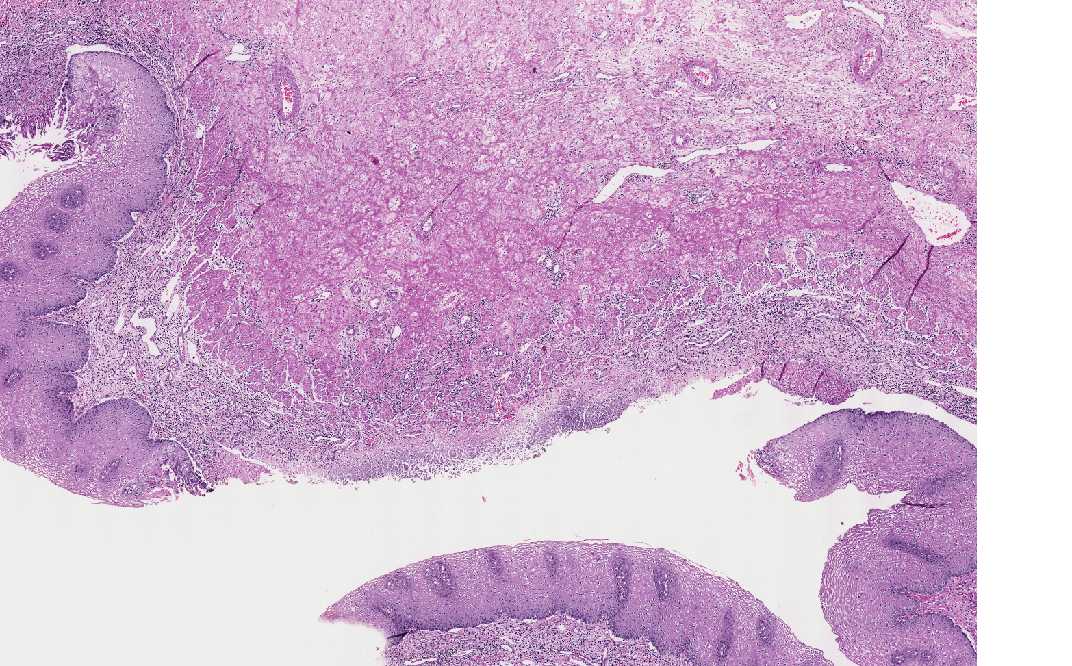

Area 1: Note that the ulcer is rimmed by intact mucosa. The ulcer is covered by a thin layer of fibrinous exudate with underlying granulation (contains a good number of neovascularization) associated with acute and chronic inflammation. Characteristically, the 3M cells (arrow) are noted in the squamous epithelium at the edge of the ulcer. It is, therefore, important to biopsy the edge of the ulcers.

• This is a resection specimen which shows several characteristic features of esophagitis caused by herpes simplex virus (herpes eesophagitis). First there are multiple ulcers (Area 1 and 2) with intervening intact mucosa (arrow). The ulcer is covered by a thin layer of fibrinous exudate with inflammatory cells. Underlying this fibrinous exudate are granulation tissue with acute and chronic inflammatory cells.